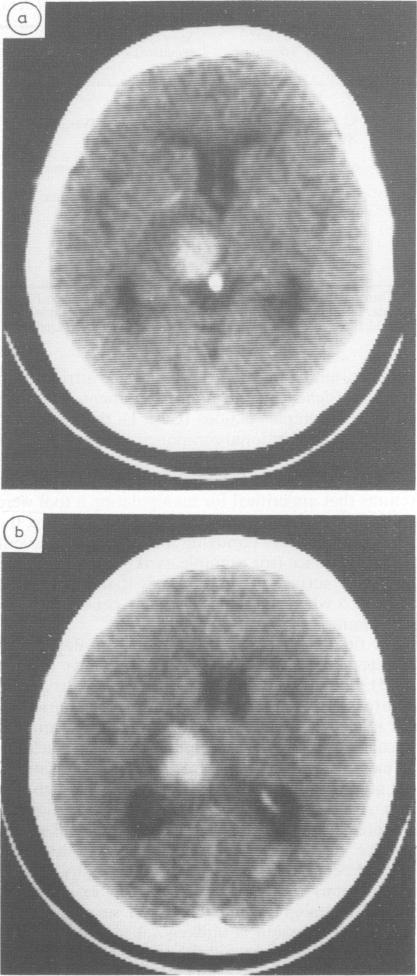

Limb apraxia was investigated with standardised tests in 14 patients whose CT scan provided evidence of a vascular lesion confined to the left basal ganglia, or the thalamus, or both, and not involving the cortex or adjacent white matter. Five patients were severely impaired in imitating movements and pantomiming object use. Four of them also performed poorly when tested with real objects. In two patients the lesion was primarily thalamic and in three the lesion was primarily in the lenticular nucleus and the posterior limb of the internal capsule. Patients without apraxia generally had smaller injuries, but there were exceptions. Apraxia is currently conceived of as due to damage of cortical areas and their cortico-cortical connections, but the present data suggest that the model should be enlarged to include the deep nuclei and the pathways running through them.

我们使用标准化测试对14例患者的肢体失用症进行了研究,这些患者的CT扫描显示血管病变局限于左侧基底神经节、丘脑或两者,且未累及皮质或相邻白质。5例患者在模仿动作和比划使用物体时严重受损。其中4例在使用真实物体进行测试时表现也很差。2例患者的病变主要在丘脑,3例患者的病变主要在豆状核和内囊后肢。没有失用症的患者损伤通常较小,但也有例外。目前认为失用症是由于皮质区域及其皮质 - 皮质连接受损所致,但目前的数据表明,该模型应扩大到包括深部核团及其之间的传导通路。